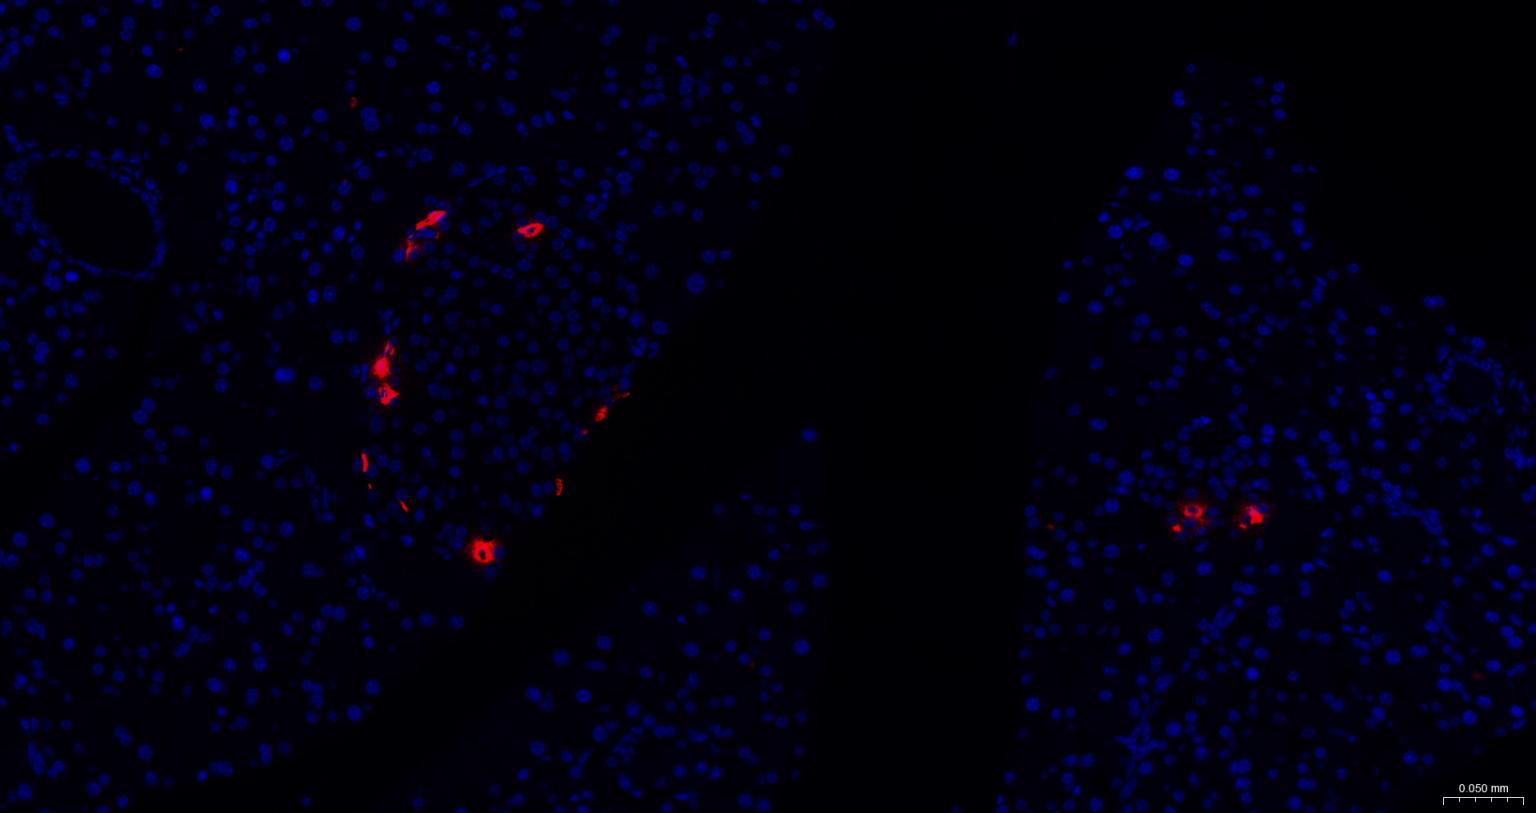

IFHuman, Mouse, Rat1:50-200

交叉反应: Human, Mouse, Rat